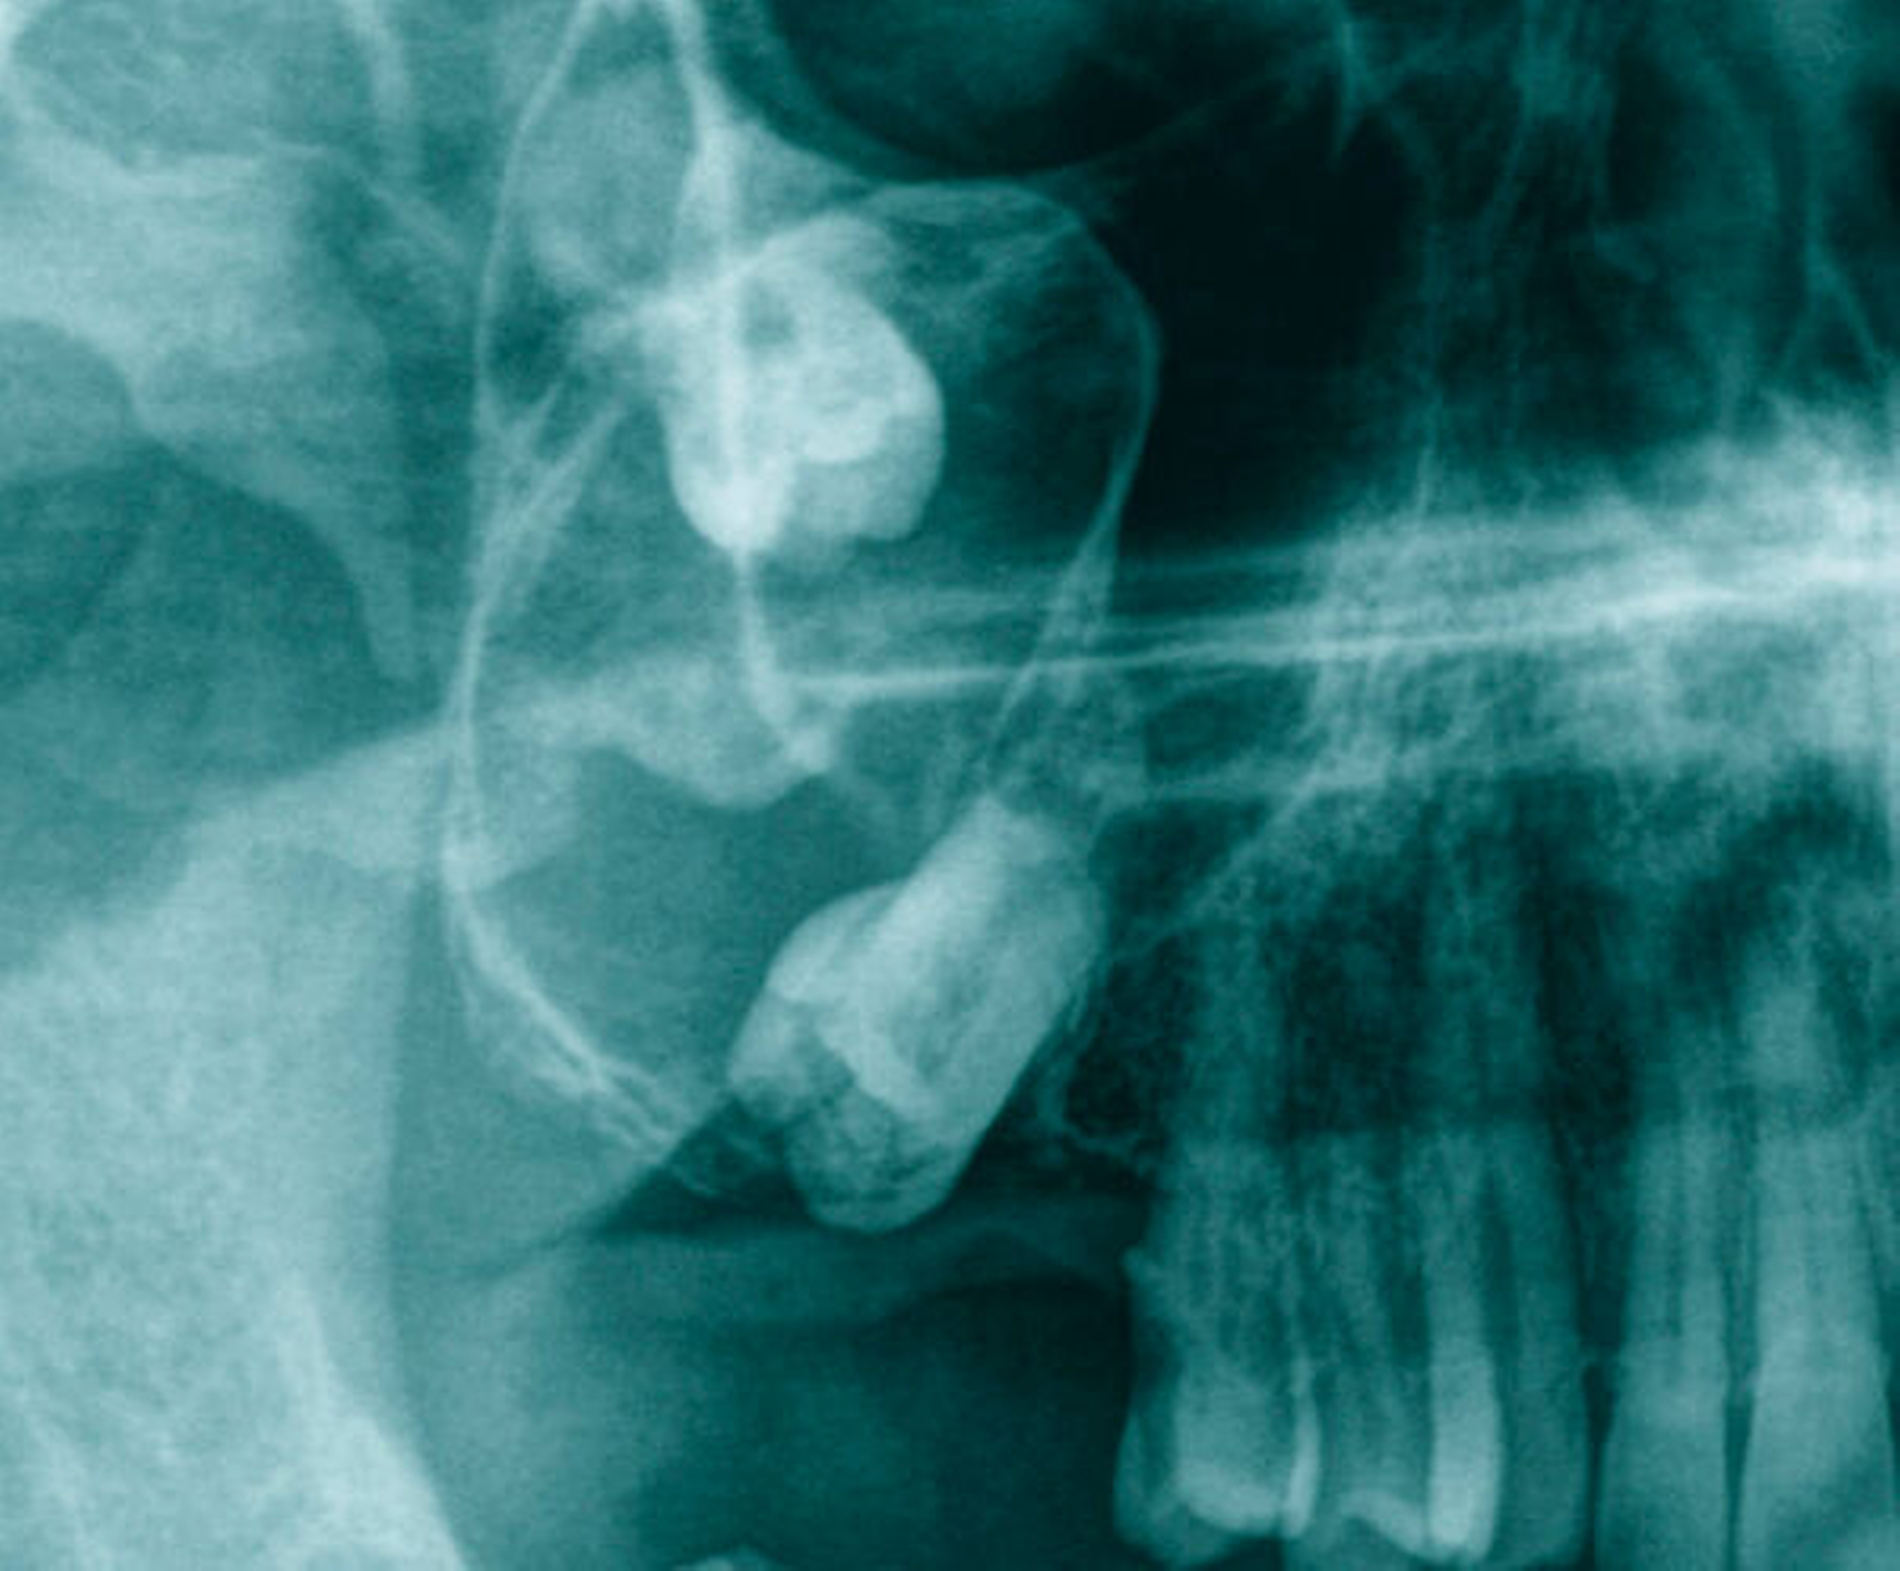

In der Panoramaschichtaufnahme (PAN) projizierten sich der Zahn 17 verlagert am unteren Rand des Sinus maxillaris und der Zahn 18 weiter cranial in der Kieferhöhle. Beide Zähne waren verbunden mit einem ovalen, scharf begrenzten Befund in der Größe einer Walnuss, der von der Krone des Zahnes 18 ausging und distoapikal am Zahn 17 endete (Abbildung 2). Zur Beurteilung wurde eine Dentale Volumentomografie (DVT) angefertigt. In der dreidimensionalen Aufnahme wurde die Ausbreitung der knöchern scharf begrenzten Raumforderung, die bis zum oberen Drittel der Kieferhöhle reichte, sichtbar (Abbildung 3).